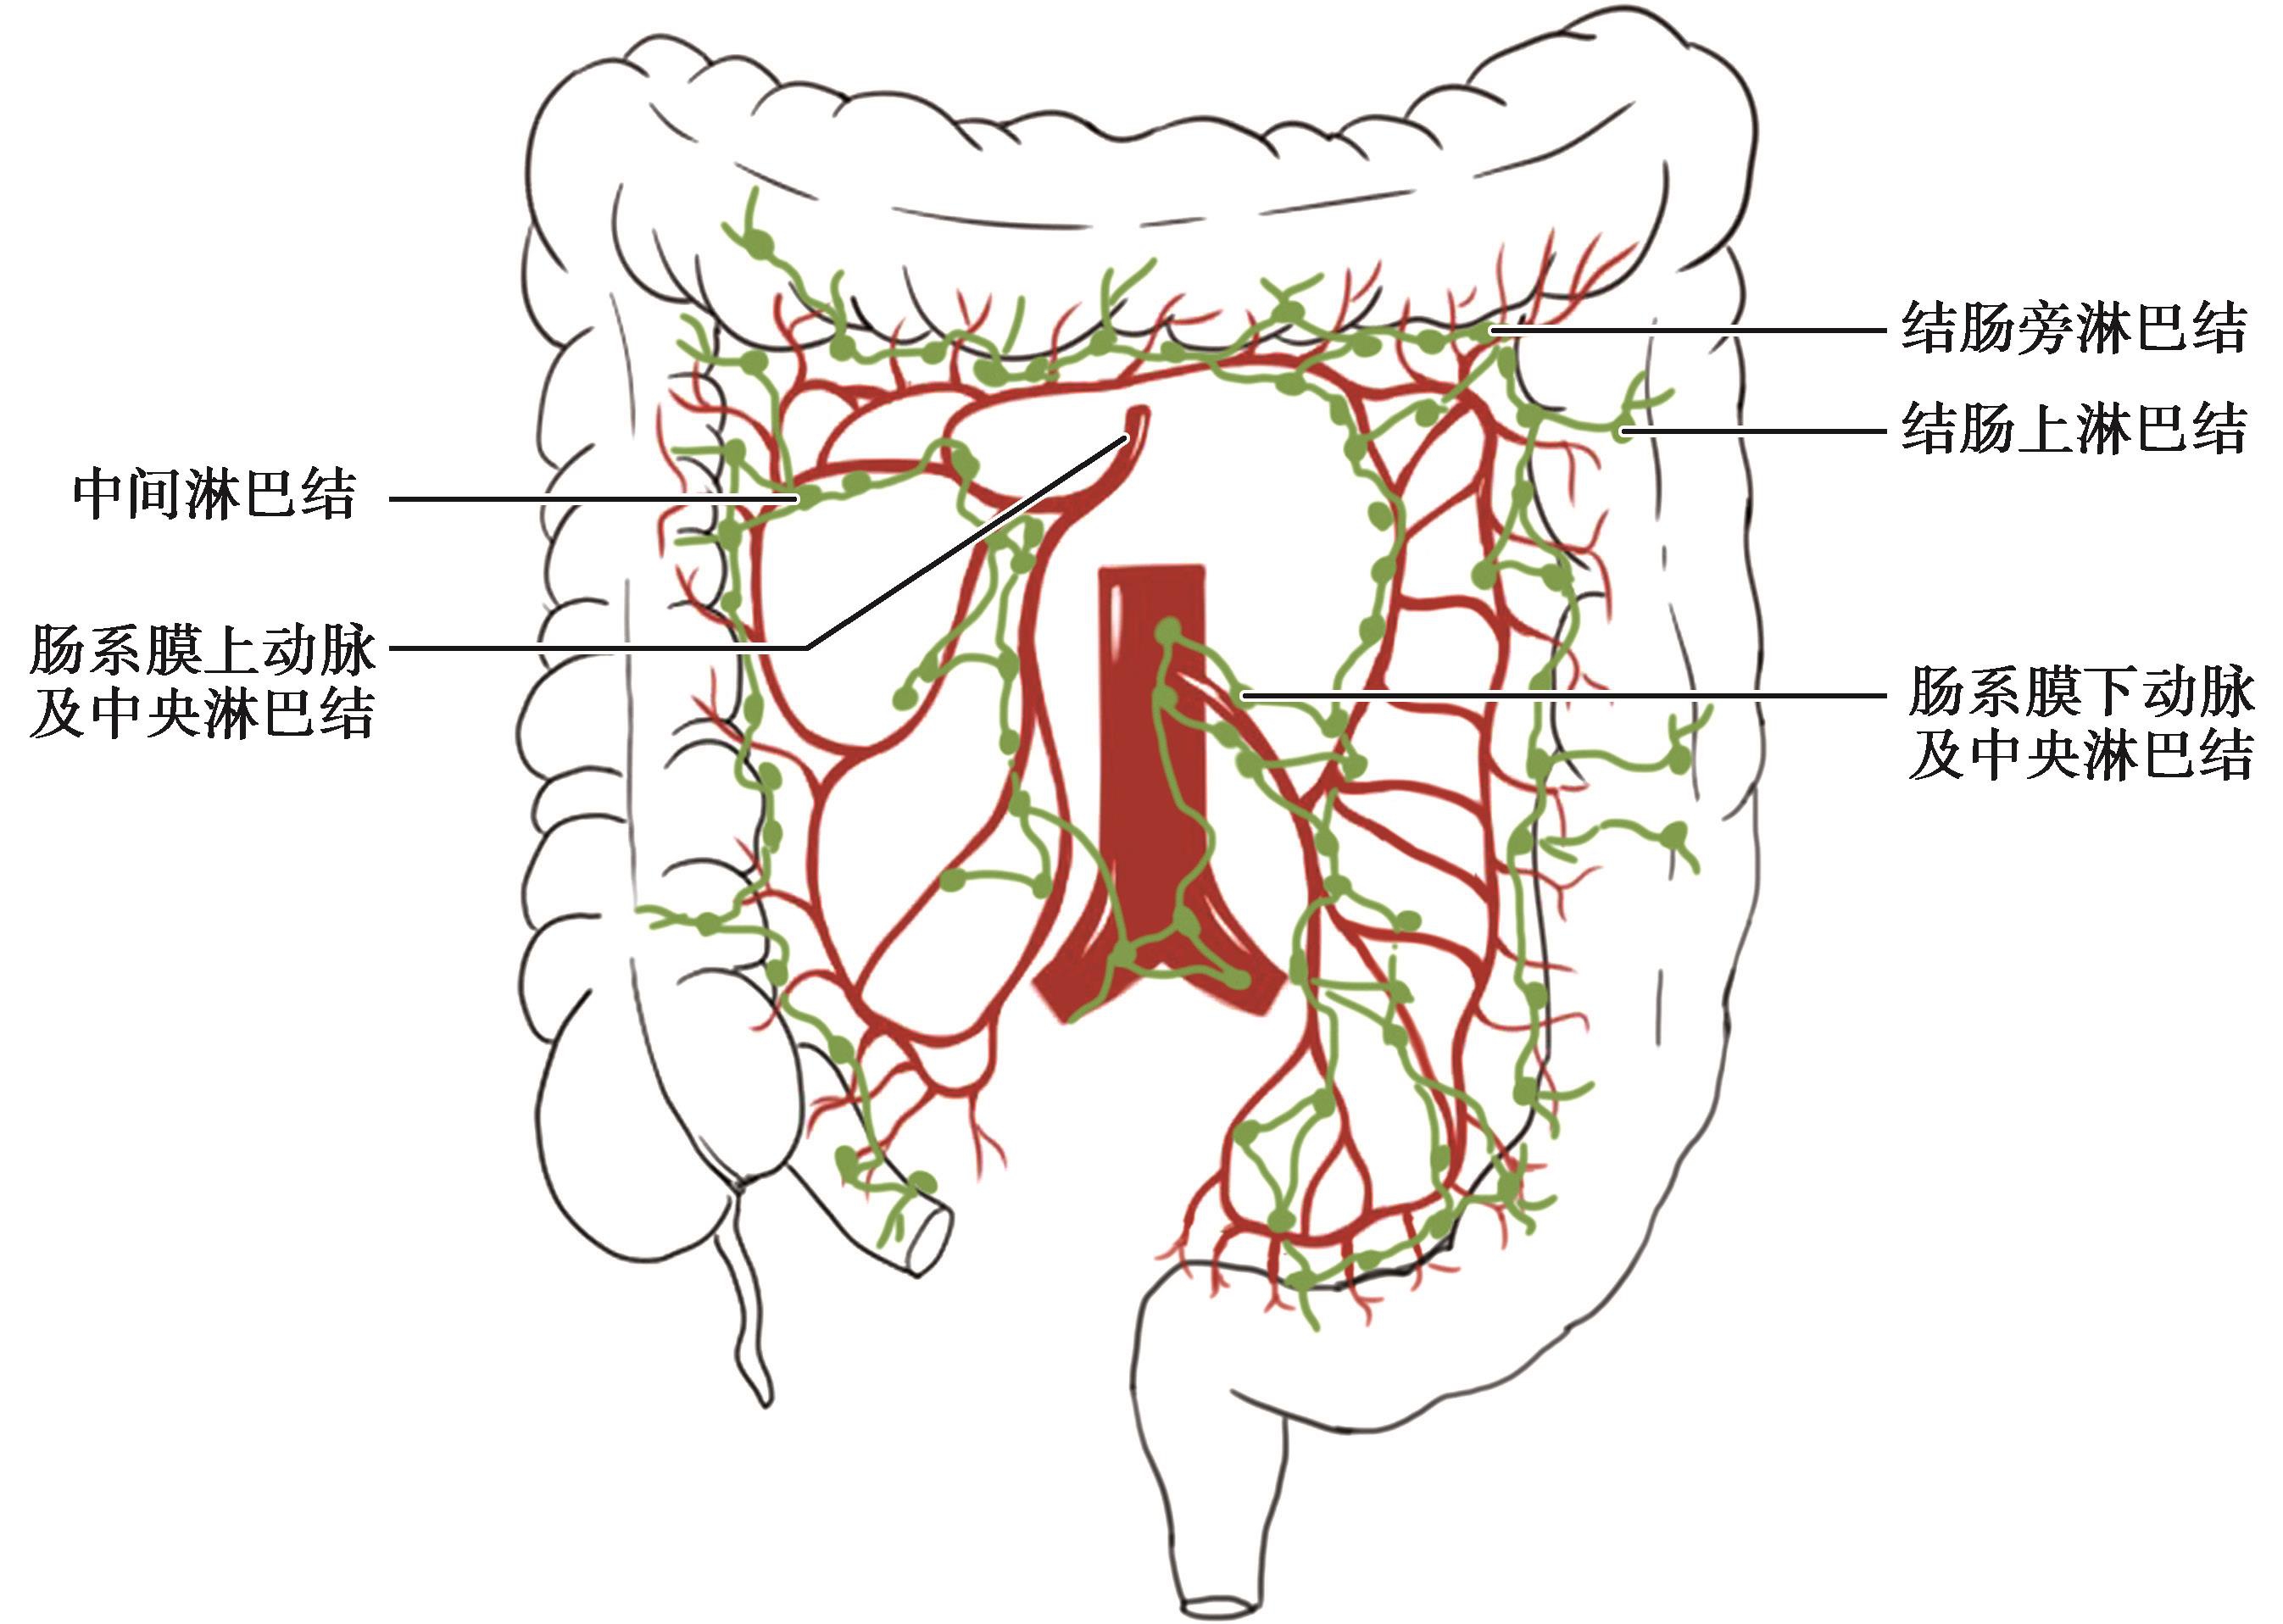

从结肠各段肠壁淋巴液到淋巴管,均循序沿着各自的血管走行,到达相应的淋巴结,然后经肠系膜上动脉根部和肠系膜下动脉根部淋巴结至腹主动脉旁淋巴结,再注入胸导管。各组淋巴结之间及邻近的淋巴结均有广泛联系,回盲部的淋巴还可经胰腺前方到达幽门下淋巴结。

图2-8 结肠的淋巴结

位于结肠壁上的肠脂垂内。

位于结肠系膜缘,伴着边缘动脉分布。

沿着结肠右、中、左动脉分布。

沿着肠系膜上动脉和肠系膜下动脉分布。